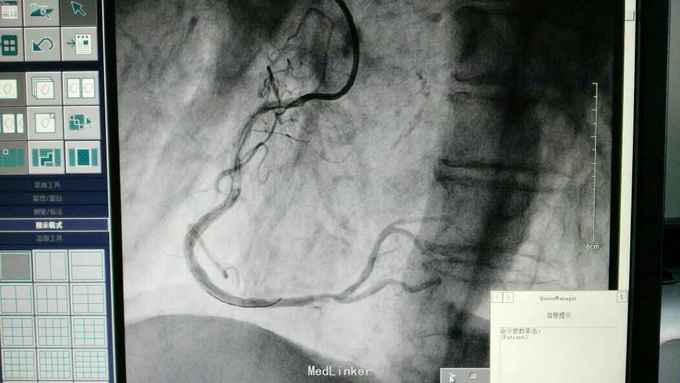

急性下壁心肌梗死,立即启动绿色通道,行急诊冠脉造影明确冠脉病变,必要时PCI治疗,行CAG示:LAD中重度狭窄,LCX尚可,RCA中段局限重度,可见前向血流,选段后降支处重度狭窄,血管钙化明显。考虑此次靶血管为RCA中段处,血管钙化迂曲明显,拟处理RCA,术中导丝到达远端后,预扩球囊反复高压扩张后,支架均无法通过,采用双导丝增加支撑依然无法通过,再更换高压后扩球囊高压扩张,锚定等,最终成功植入支架

急性心梗有时候处理相对较容易,但此病变在于血管钙化迂曲明显,且再次详细阅片后发现局部有“礁石”样病变,预扩球囊及后扩球囊不易扩张,有时需切割或旋磨,但对于急性心梗,如果血流达到理想级别,可不勉强处理,急性心梗中,有些病变为固定狭窄基础上急性血管闭塞,处理并非如一般血栓病变那样容易,造影后仍然需要详细阅片,根据具体病变情况选择合适手术处理方法